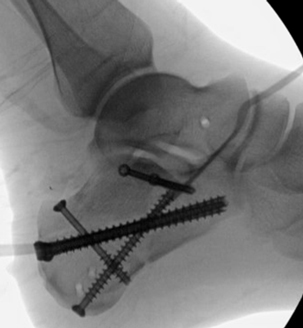

TOTAL ANKLE REPLACEMENT :: ORIF CALCANEUS :: ORIF ANKLE FRACTURE DISLOCATION :: COMPLEX BUNION AND LESSER TOE CORRECTION :: TALUS FRACTURE -1 :: TALUS FRACTURE -2 :: LISFRANC REPAIR :: COMPLEX TRIPLE ARTHRODESIS 1 :: COMPLEX TRIPLE ARTHRODESIS 2 :: MINIMALLY INVASIVE BUNION REPAIR 1 :: MINIMALLY INVASIVE BUNION REPAIR 2 :: ARTHROSCOPIC CARTILAGE REPAIR :: TENEX SPUR DEBRIDEMENT :: Haglunds Debridement and Achilles Repair